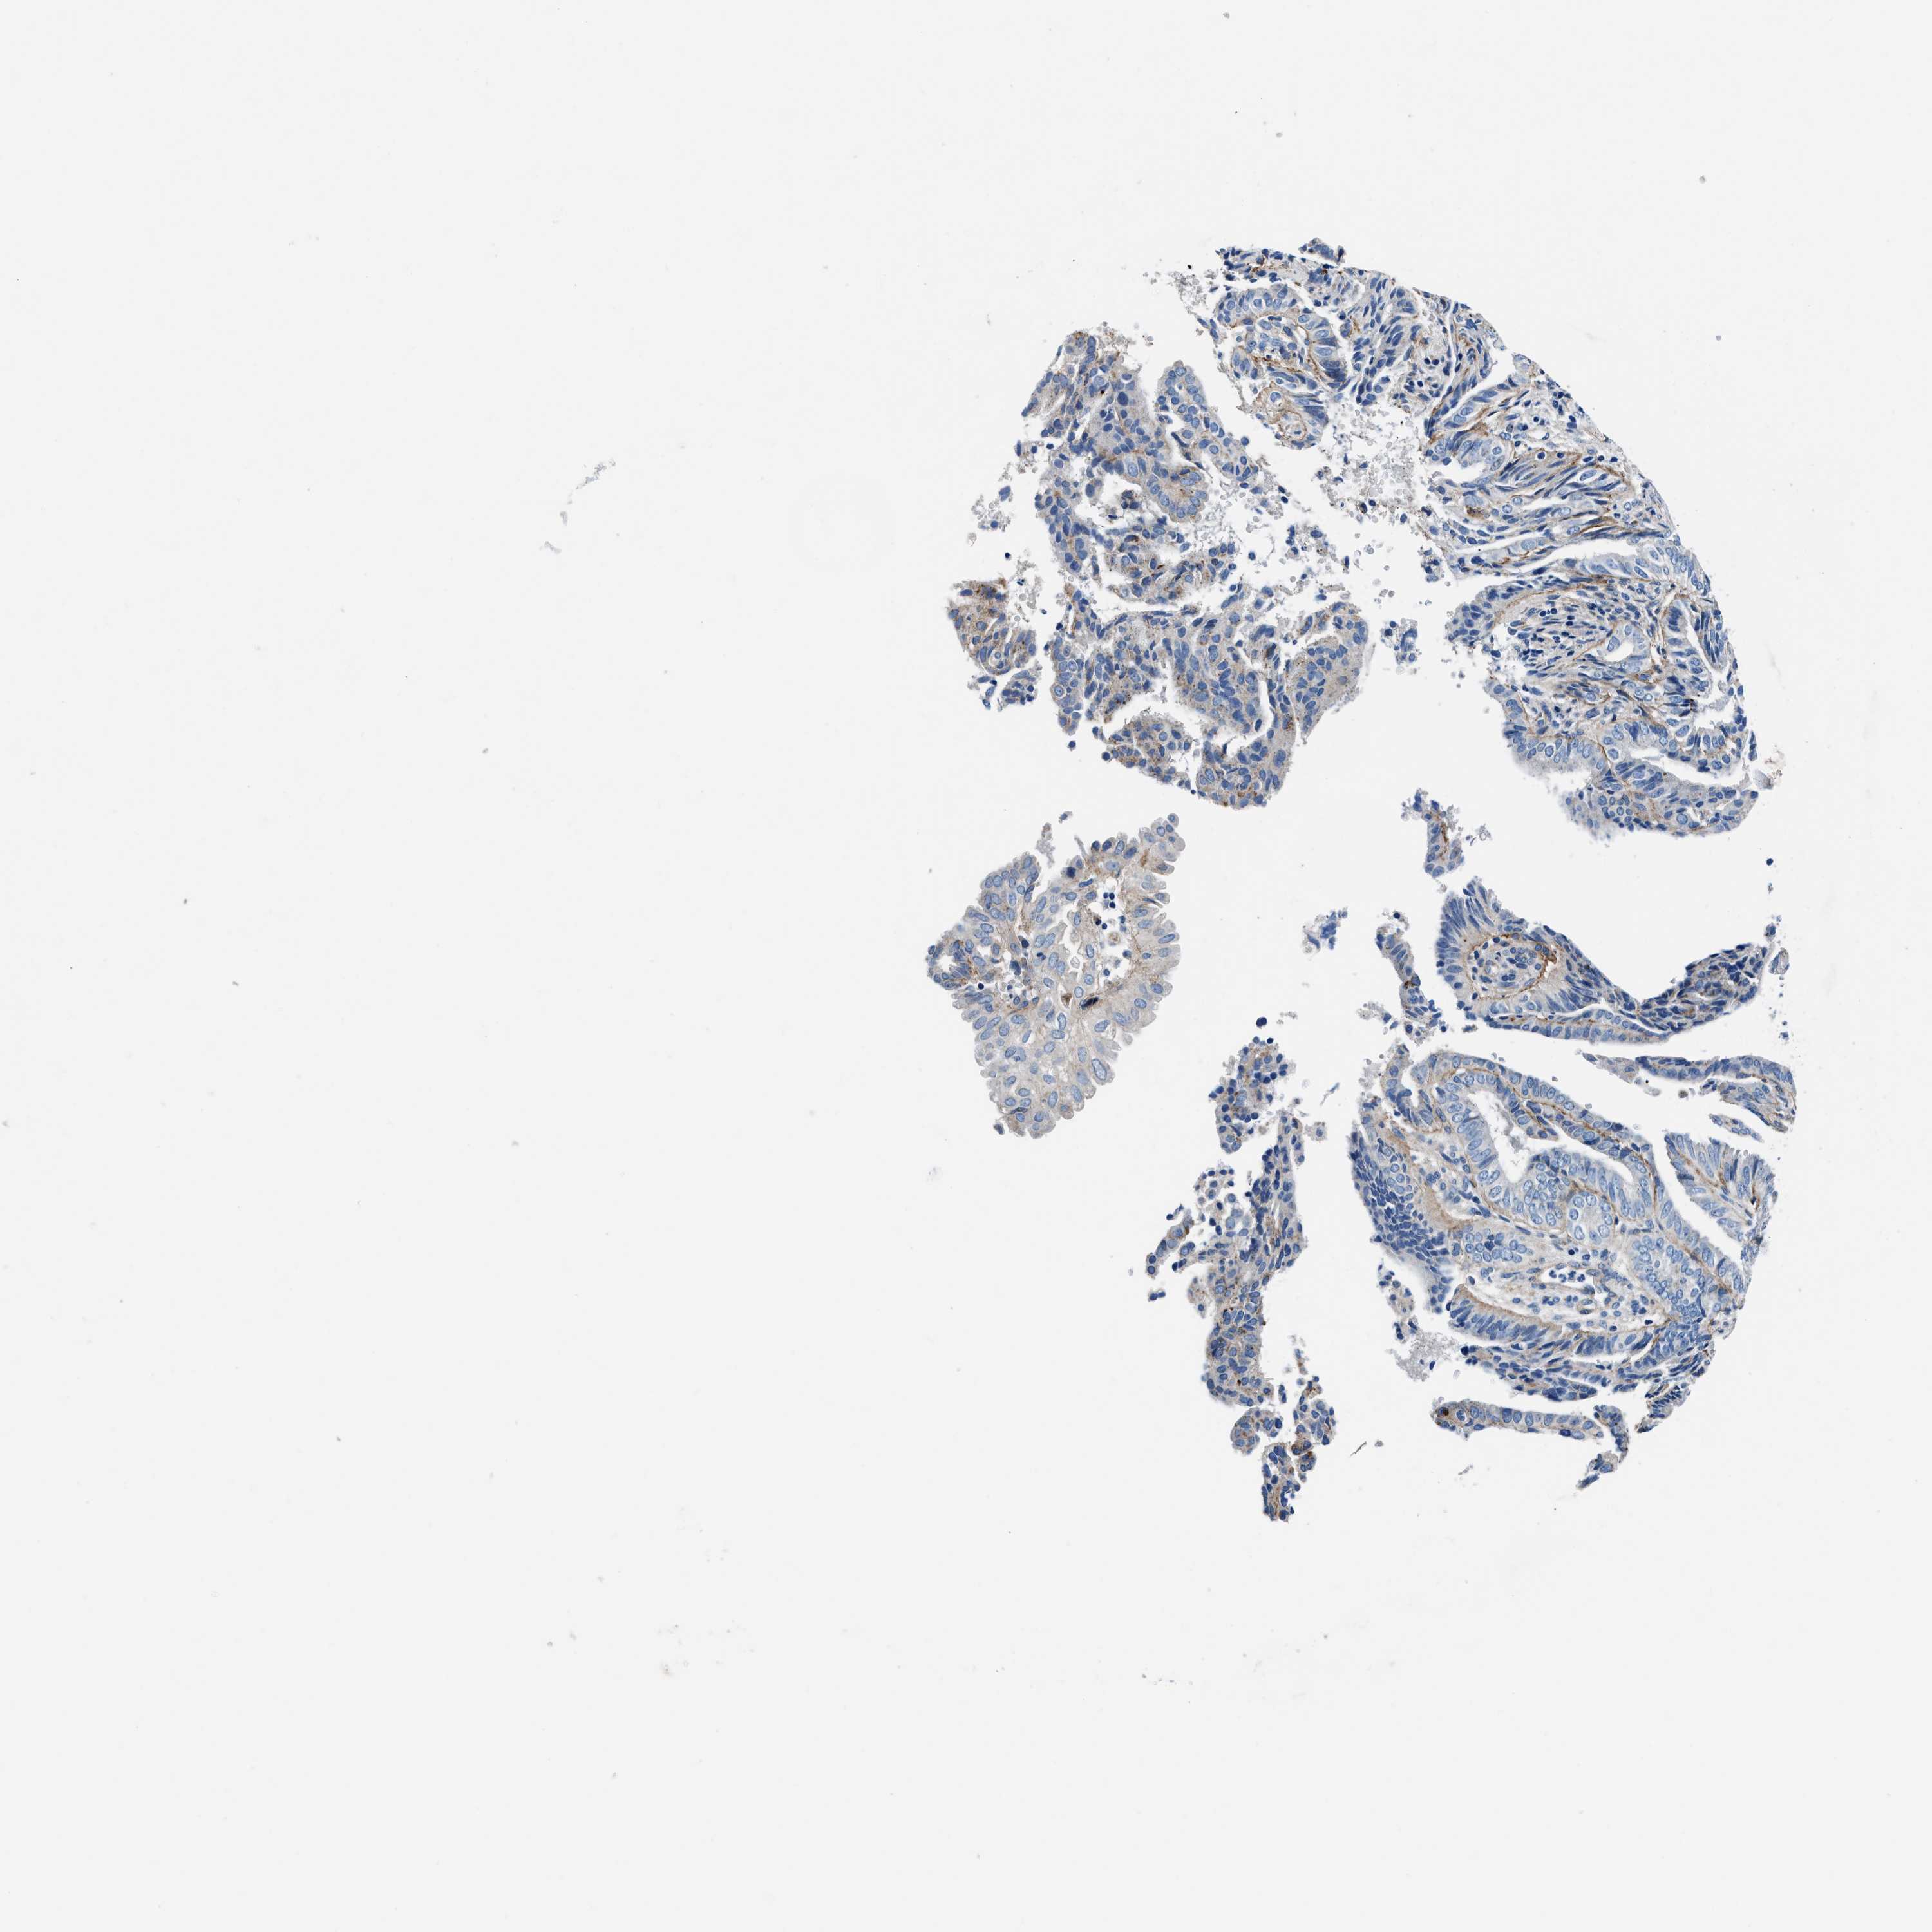

ENDOMETRIAL CANCER - Protein expressioni

A mouse-over function shows sample information and annotation data. Click on an image to view it in a full screen mode. Samples can be filtered based on level of antibody staining by selecting one or several of the following categories: high, medium, low and not detected. The assay and annotation is described here.

Note that samples used for immunohistochemistry by the Human Protein Atlas do not correspond to samples in the TCGA dataset.

Antibody stainingi

Antibody staining in the annotated cell types in the current human tissue is reported as not detected, low, medium, or high, based on conventional immunohistochemistry profiling in selected tissues. This score is based on the combination of the staining intensity and fraction of stained cells.

Each image is clickable and will lead to virtual microscopy that enables deeper exploration of all samples and also displays staining intensity scores, fraction scores and subcellular localization as well as patient and tissue information for each sample.

Antibody CAB001960

Antibody CAB016353

Staining

High

Medium

Low

Not detected

Intensity

Strong

Moderate

Weak

Negative

Quantity

>75%

75%-25%

<25%

None

Location

Nuclear

Cytoplasmic/membranous

Cytoplasmic/membranous,nuclear

Adenocarcinoma, NOS